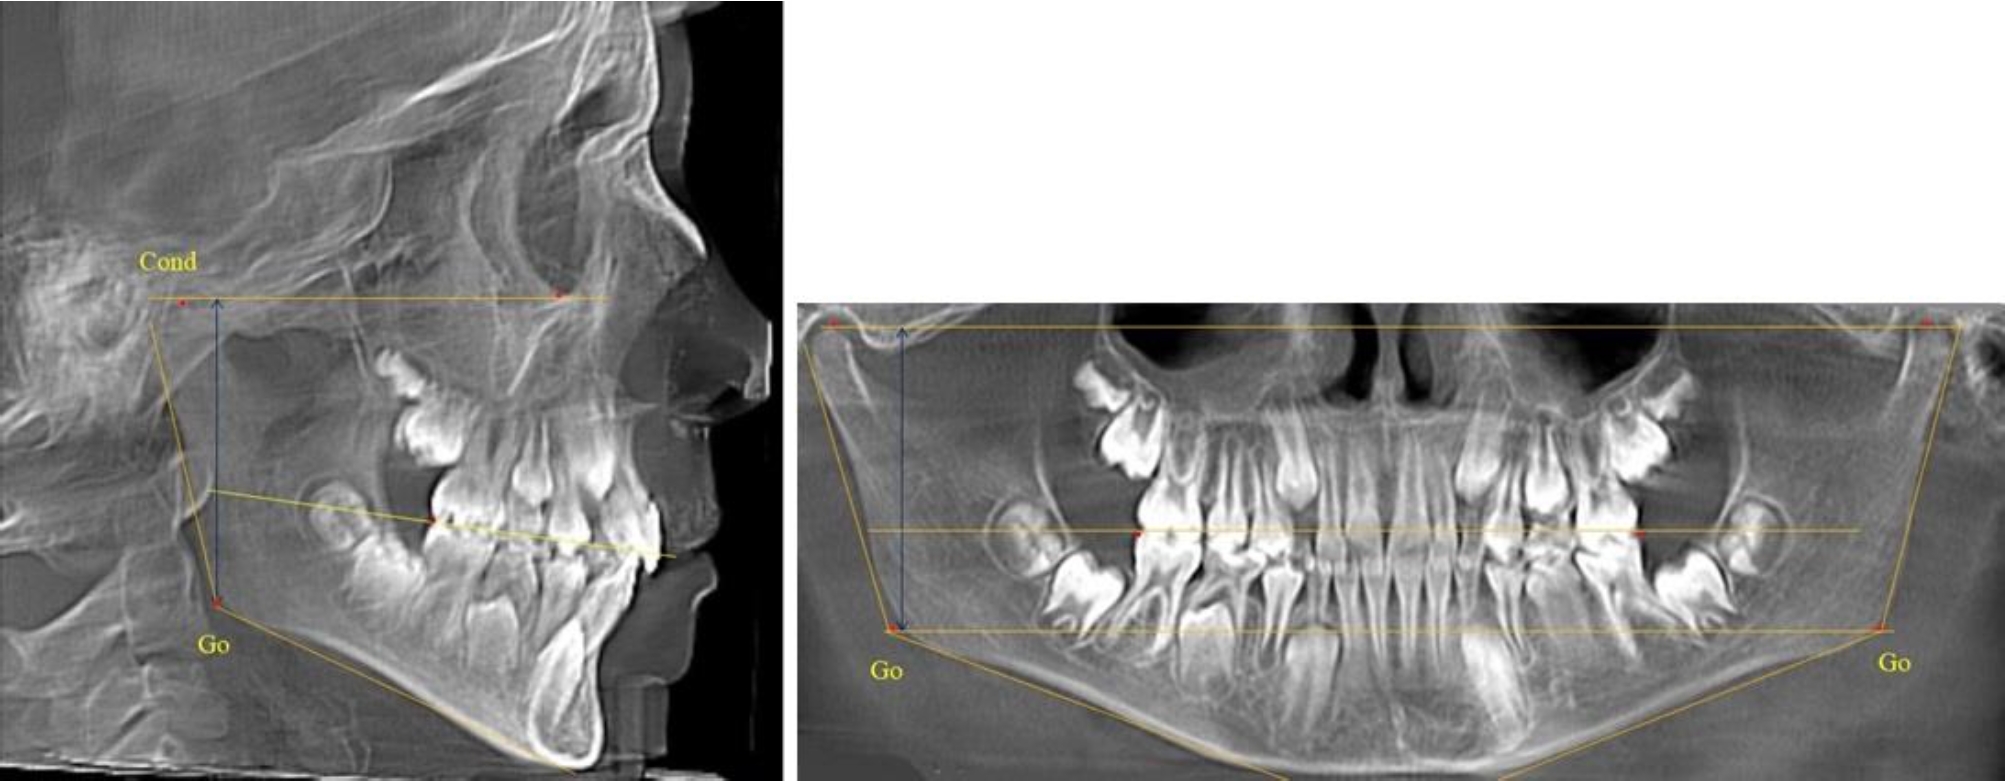

В 3-й группе были проанализированы 9 телерентгенограмм и 9 ортопантомограмм, что составило (8,49 ± 2,71) % от числа изученных рентгенограмм (рис. 3).

Рис. 3. ТРГ и ОПТГ пациента после смены молочных резцов

На всех рентгенограммах произошла смена молочных резцов постоянными. Окклюзионная линия делила ветвь на два отдела.

Высота ветви у детей у детей 3-й группы составляла (51,07 ± 2,72) мм, что было достоверно больше, чем у детей 1-й группы (р ˂ 0,05). При этом высота верхней окклюзионно-суставной части была (29,06 ± 1,44) мм, а нижней – (22,01 ± 1,59) мм. Высота верхней части была больше нижней, что и определяло особенности соразмерности частей ветви нижней челюсти в анализируемый возрастной период.

Относительные показатели соразмерности частей ветви нижней челюсти показали, что отношение высоты верхней части ветви к нижней в среднем составляло 1,32 ± 0,14. Отношение общей высоты ветви к верхней ее части составляло 1,75 ± 0,12, а отношение общей высоты ветви к нижней ее части было 2,32 ± 0,17, что и определяло особенности соразмерности частей ветви нижней челюсти в анализируемый возрастной период.

В 4-й группе были проанализированы 12 комплектов рентгенограмм, что составило (11,32 ± 3,08) % от общего числа. На всех рентгенограммах произошла полная смена всех молочных зубов постоянными. Окклюзионная линия делила ветвь на два отдела (рис. 4).

Рис. 4. ТРГ пациента после смены всех молочных резцов

Высота ветви у детей 4-й группы составляла (54,27 ± 2,59) мм, что было достоверно больше, чем у детей 1-й группы (р ˂ 0,05). При этом высота верхней окклюзионно-суставной части была (32,51 ± 1,72) мм, а нижней – (21,76 ± 1,42) мм. Высота верхней части была больше нижней, что и определяло особенности соразмерности частей ветви нижней челюсти в анализируемый возрастной период.

Относительные показатели соразмерности частей ветви нижней челюсти показали, что отношение высоты верхней части ветви к нижней в среднем составляло 1,49 ± 0,12. Отношение общей высоты ветви к верхней ее части составляло 1,67 ± 0,14, а отношение общей высоты ветви к нижней ее части было 2,49 ± 0,15, что и определяло особенности соразмерности частей ветви нижней челюсти в анализируемый возрастной период.